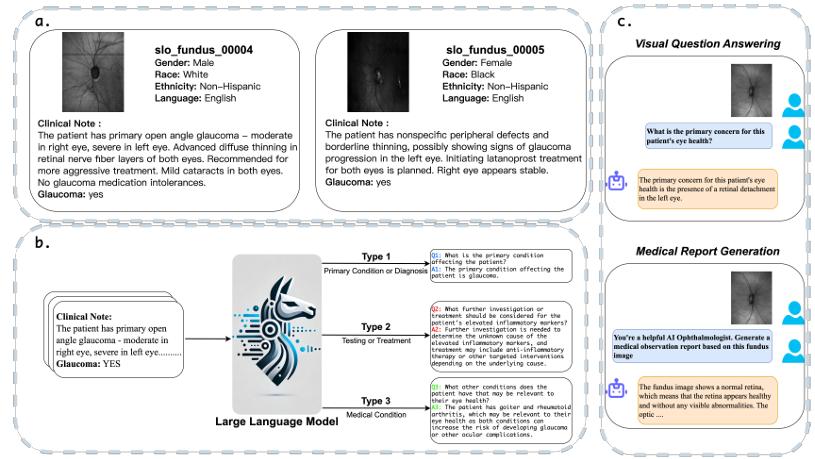

Peiran Wu, Che Liu, Canyu Chen, Jun Li, Cosmin I Bercea, Rossella Arcucci.

[paper]